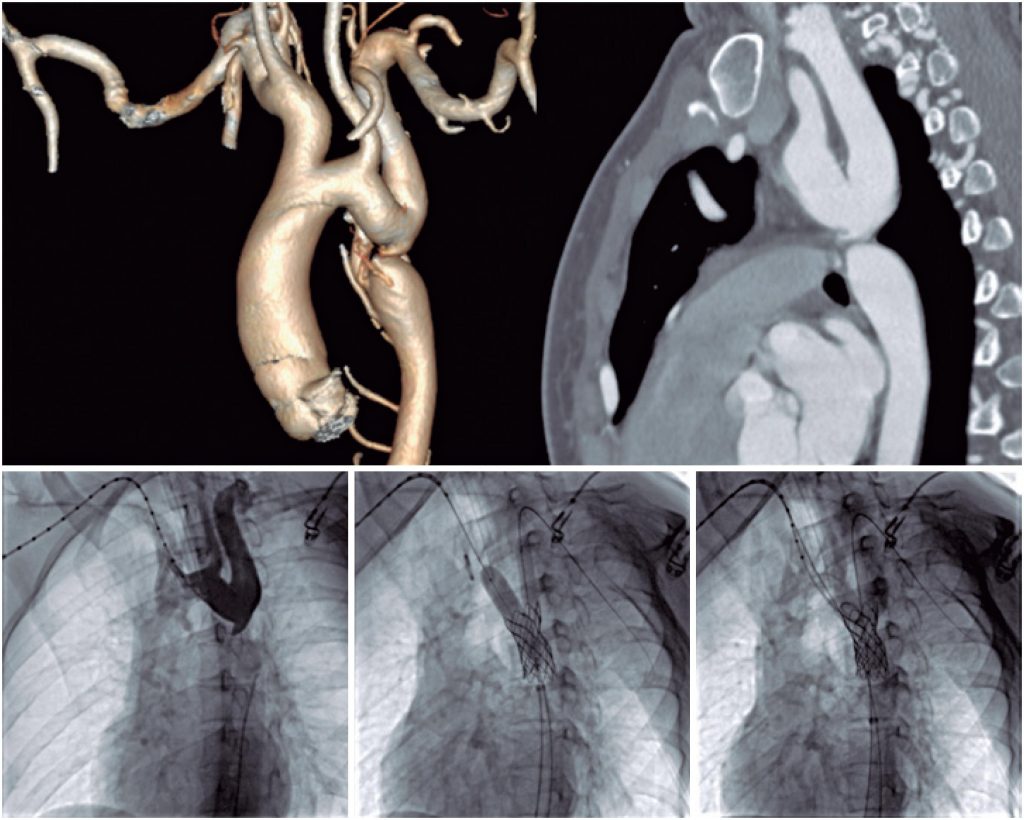

Tratamento transcateter de coarctação com atresia do lúmen aórtico e kissing balloon entre aorta e artéria subclávia esquerda

O tratamento percutâneo da CoA associada à atresia do lúmen aórtico (ALA) é um desafio técnico que exige materiais específicos e está associado a maior risco de complicações. Farjat Pasos et al. descreveram a técnica de cruzamento da CoA assistido por eletrocautério, uma opção acessível quando não é possível cruzar com guias 0,014” dedicadas ao tratamento de oclusões crônicas com a técnica tradicional. Nesses casos, está indicado o implante de stents cobertos. Habitualmente, o estreitamento da aorta é distante da origem da artéria subclávia esquerda (ASCE), permitindo que o implante do stent seja realizado sem maiores dificuldades. Nos casos em que a estenose esteja próxima da ASCE, pode-se utilizar a técnica do kissing balloon final (KBF) ou a do duplo guia para implante do stent, garantindo a permeabilidade do ramo.